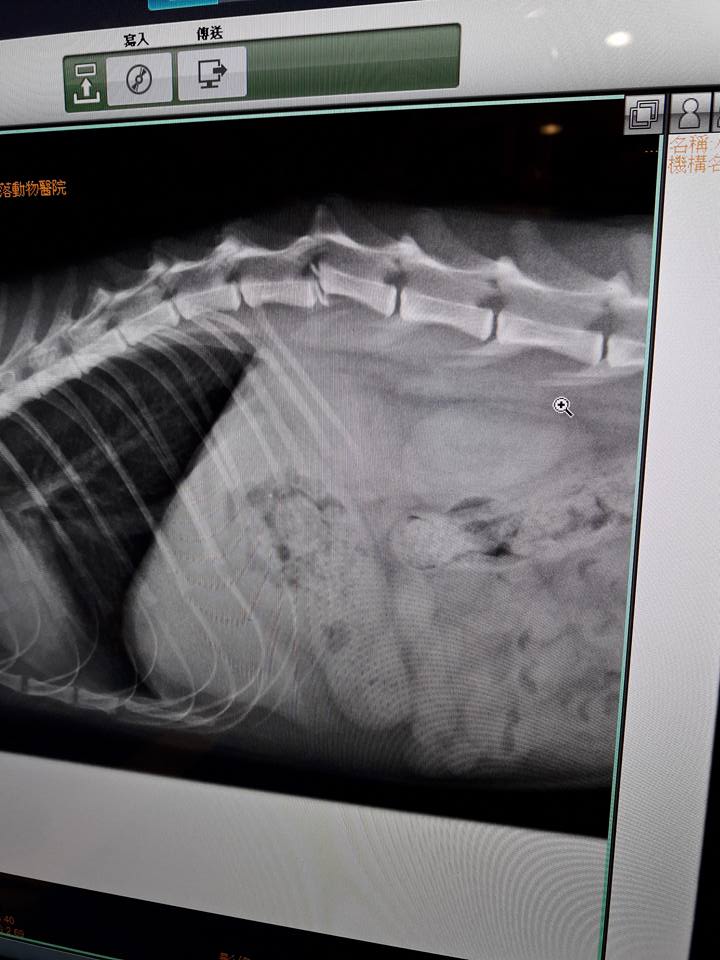

主題: 東湖市場TNR浪貓脊椎骨折手術後復健治療 申請者姓名: lois tsai 花色: 申請日期: 2017-04-16 01:18:27 申請者部落格: 申請者臉書網址: 所在縣市/合作醫院: 台北市/澄諾動物醫院 治療費用: 38300元 需求人數: 40人 已結案 (2024-06-01 13:33:25) 報名人員: We We Lin x2(已付款)、王琇盈(已付款)、Bear(已付款)、Helen Chou(已付款)、Liyin Liao(已付款)、christie(已付款)、Lichen Liao x2(已付款)、Joan Tseng(已付款)、薇薇安(已付款)、Judy(已付款)、Trista Kao(已付款)、黃ㄚ銘(已付款)、黃ㄚ銘(已付款)、Adeline Chen(已付款)、Naommi(已付款)、Diana Ting(已付款)、VICTORIA CHOU(已付款)、張雅筑(已付款)、mavis(已付款)、Midori(已付款)、chucl(已付款)、Anna(已付款)、Lawrence(已付款)、Helen Yu(已付款)、EC(已付款)、Vicky Wu(已付款)、Iris Ji(已付款)、Yi-ling Lu(已付款)、Cherry Wang x2、Cherry Wang x2(已付款)、林小豬(已付款)、HAHA(已付款)、Chihchia Chang(已付款)、小娜(已付款)、Sophia Peng x2(已付款)、Monica Wang(已付款)、Choco Chen(已付款)、 候補人員: 動物病情說明: 東湖市場已TNR兩年的貓咪小恢

在還沒通報醫助前我先帶她到角落動物醫院照X光及血檢確定是脊椎骨折錯位

二月底在台大神經科吳醫師進行手術後已轉往澄諾動物醫院後續治療及復健